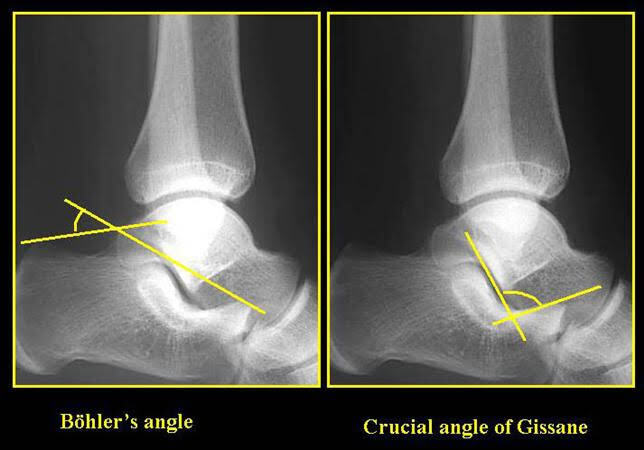

Normal value for Bohler angle and critical angle of Gissane (degrees) for calcaneal fracture assessment

A

20-40 and 120-140